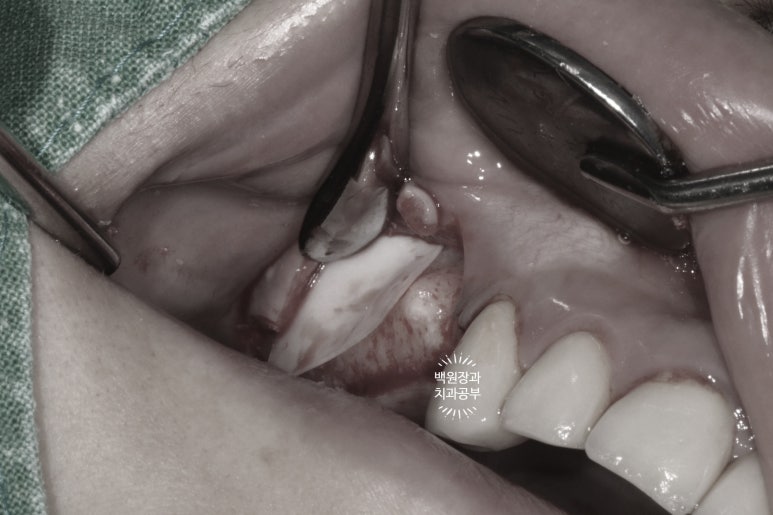

신경치료 후 크라운으로 씌웠던 치아셨는데, 이차충치로 인해 치아가 부러진 그 자리엔 짧은 뿌리 뿐이었습니다..

어금니가 없이 앞니로만 너무 오래 식사를 하시면, 이렇게 앞니가 부러짐을 경험하게 되시죠..

보시면 부러진 치아의 일부는 잇몸 속까지 포함해서 부러진 것을 볼 수 있었습니다.